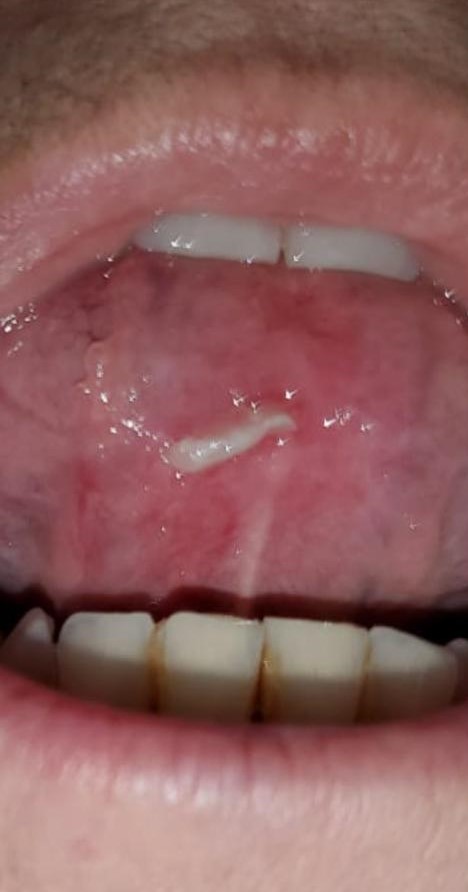

Lesión por rozamiento dentario